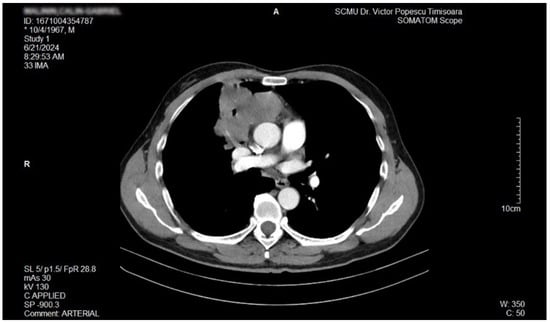

The proposal for H. pylori eradication treatment was initially postponed by the patient. However, the patient received symbiotics in order to alleviate the gut microbiota dysbiosis and also DAO supplementation, aiming at reducing the systemic effects of bacterial histamine overproduction. Further imaging studies were, however, ordered in the context of persistent, treatment-resistant pruritus that lasted for more than 6 weeks and eventually became suspicious for a malignancy. So that thorax and abdomen computed tomography (CT) were recommended and performed soon after, on 21 June 2024. As depicted in Figure 3, Figure 4 and Figure 5, a large right mid-thoracic tumoral formation with mediastinal extension of 7.8 cm/5 cm and a satellite lymph node of 7 mm placed in the anterior aspect of the upper right pulmonary lobe were discovered. The image was considered highly suspicious of lymphoma or pulmonary malignancy.

Figure 3.

Contrast thorax CT: large right midthoracic tumor with mediastinal extension.(axial view.